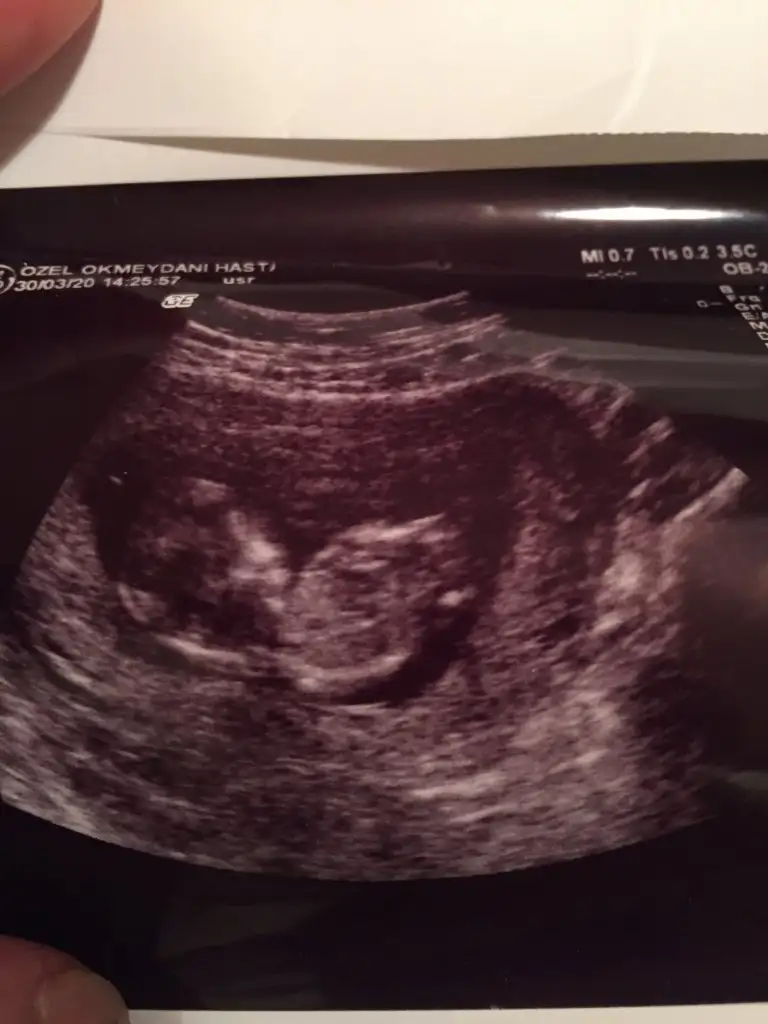

Meraba.12+1 iz cinsiyetini tahmin edebilirmisiniz

Buradaki fotoda 7 haftalıkken.karindan ultrason.bi önceki resimlerde doktor 12 haftalıkken kararsız kaldı.net birşey söyleyemedi.

ikili tarama sonrası. Sizce cinsiyeti nedirr? Doktor bi tahmin de bulundu ama daha erken tabi ☺️☺️

ikili tarama sonrası. Sizce cinsiyeti nedirr? Doktor bi tahmin de bulundu ama daha erken tabi ☺☺

Usg net değil emin olmadım başka usg de paylaşın 12 13 hafta olursa şimdilik sanki erkek gibi gibi 😬